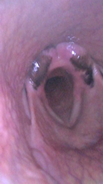

In the animal with an ocular tumor and infra-auricular metastasis (Figure 1), we noticed the collapse of the palatopharyngeal arch, epiglottic entrapment, vascular increase of the left pharyngeal wall (corresponding side of the tumor), flaccidity of the rostral pharyngeal constrictor muscle, palatal flaccidity, where all the findings are consistent with the innervation corresponding to pairs IX, X and XII, where we cannot fail to mention the muscles that tense and elevate the soft palate, which in Figures 4 and 5a,b) shows its complete collapse.

Figures 4, 5(a, b), 6 We notice complete epiglottic entrapment, collapse of the palatal arch, vascular enlargement of the right pharyngeal wall -side of the tumor.

Figure 5a Palatal collapse.

The complex innervation of the oropharyngeal region has its main origin in pairs IX, m.elevator veli palatini, m.constrictor pharyngeus rostral, m.pterigo pharyngeus and m.palatopharyngeus8–12 which may be of great importance in the equine species and still very little studied as the findings in the bovine species are very compatible with respiratory problems in horses with low performance, such as epiglottic entrapment and palatal collapse. In cattle with epiglottic entrapment (Figure 5a and 5b) we can say that the palatal tensor no longer maintains the aforementioned functional structure, but in cattle of little clinical importance or still little known, but in equine athletes of vital importance; the IX pair arises outside the central nervous system in the posterior region of the parotid gland, which explains the choice of cattle with tumors in this region, as well as the VII, VIII, X, XI and XII pairs, as well as all their respective branches that from what this experiment showed, based on the endoscopies performed, the lesions mainly in the muscles that tension the soft palate, dorsal palatal region, even with unilateral tumoration have a response, in the oropharyngeal muscles examined, bilaterally, but more accentuated on the corresponding side of the presence of the tumor (Figure 7).

Comparatively, we can make some parallels between the images of equine epiglottic entrapment (Figure 7–10), collapse of the palatal arch (Figure 7), low muscle tension of the soft palate (Figure 10), unilateral edema of the cuneiform recess (Figure 7) , in cattle with findings in horses with low performance with etiology in the upper portion of the airways or oropharynx, where the comparative study proved to be an interesting model for the study of the anatomical structures involved in the "sagging" of the soft tissues of the upper airways in horses and apparently of not well understood importance in cattle, where these processes reduce airflow in the respiratory tract. In horses, we can explain that this loss of palatal and oropharyngeal tone, in general, the regional lymph nodes are in contact with the pharyngeal branches of the glossopharyngeal and vagus nerves and retropharyngeal lymphadenopathy (increased volume and infra-auricular tumoration, Figure 1,2) could result in compression and irritation,11 a very important fact for equine athletes but apparently not so important in cattle, as they, with the presence of large tumors, did not show signs of dyspnea, respiratory discomfort or even any form of postural compensation to improve breathing.

Figure 10 Bovine soft palatal collapse. These images show the similarity of problems in two species - cattle and horses.